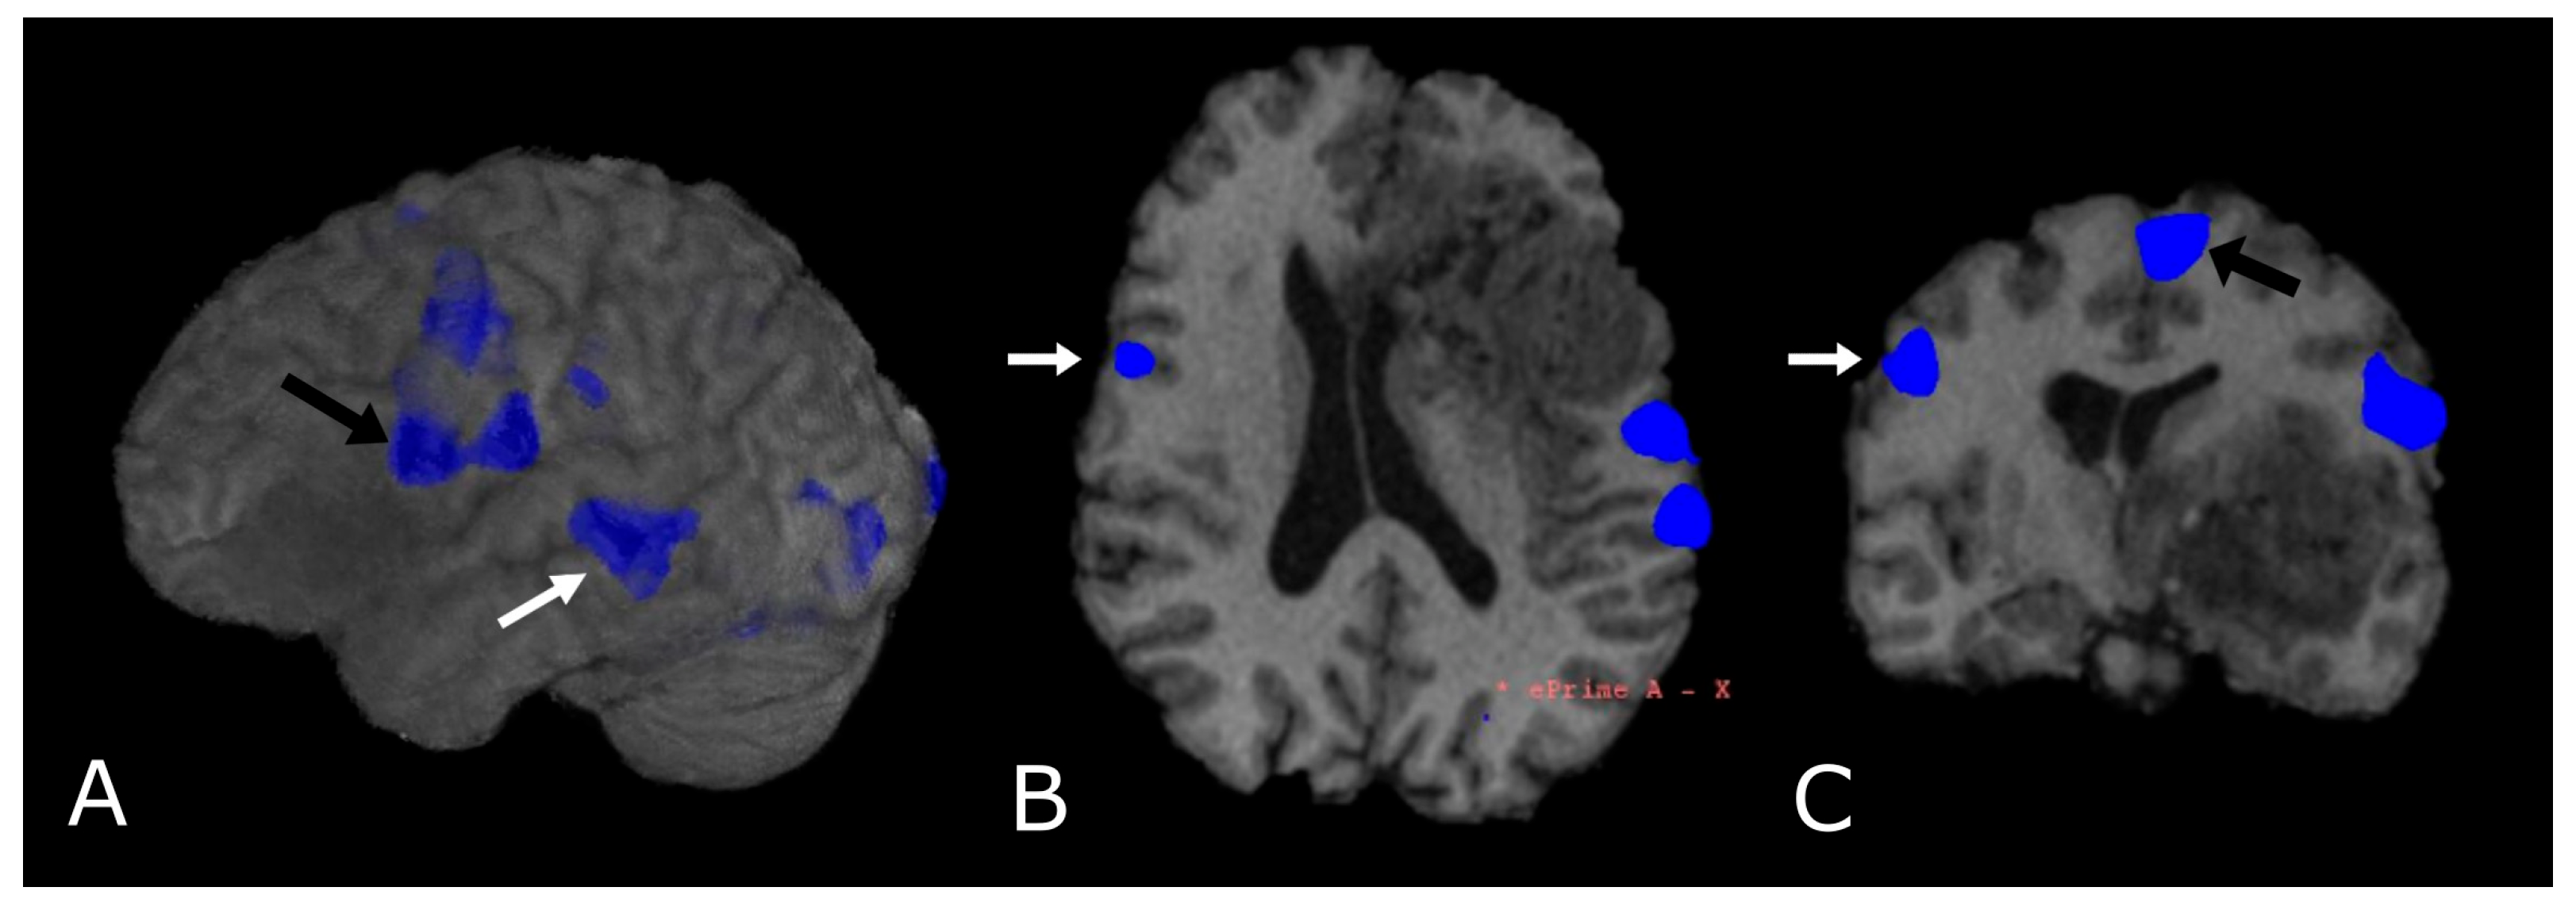

Figure 12.

Language task-based fMRI. fMRI correlation maps of cortical activation during language tasks in a patient with frontal-temporal-insular GB. Blue represents areas of increased cortical activation. (A) 3D surface rendering with BOLD signal overlay reveals the activation of Broca’s Area, displaced posteriorly by the lesion (black arrow; expressive speech) and in the superior temporal gyrus (white arrow, Wernike’s Area, receptive speech); (B,C) Axial and coronal deskulled T1w-BRAVO with BOLD signal overlay confirm the activation and the dislocation of Broca’s Area and shows a significant but smaller activation in the right inferior frontal gyrus (white arrow’s head). Black arrow’s head indicates the supplementary Motor Area (C).